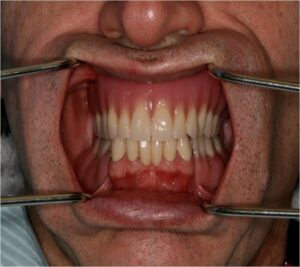

- Ακινητη προσθετικη, δηλαδη στεφανες και γεφυρες

- Προσθετικη επι εμφυτευματων